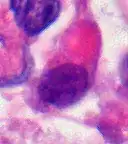

Hämatoxylin-Eosin gefärbtes Schnittpräparat. Originalvergrößerung 1:400